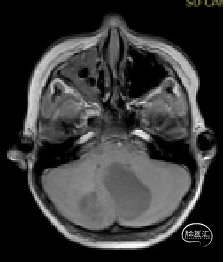

术前MRI

现病史:患者18个月前无明显诱因出现间断头痛,休息后可缓解,开始未予重视,未行特殊治疗。1周前患者无明显诱因出现恶心、呕吐,就诊于当地医院,行颅脑MRI提示:小脑囊实性占位性病变,首先考虑毛细胞星型细胞瘤。现患者为求进一步治疗就诊于我院,门诊以“脑肿瘤”收入院。患者自发病以来神志清,精神可,饮食睡眠正常,二便如常,体重未见明显下降。